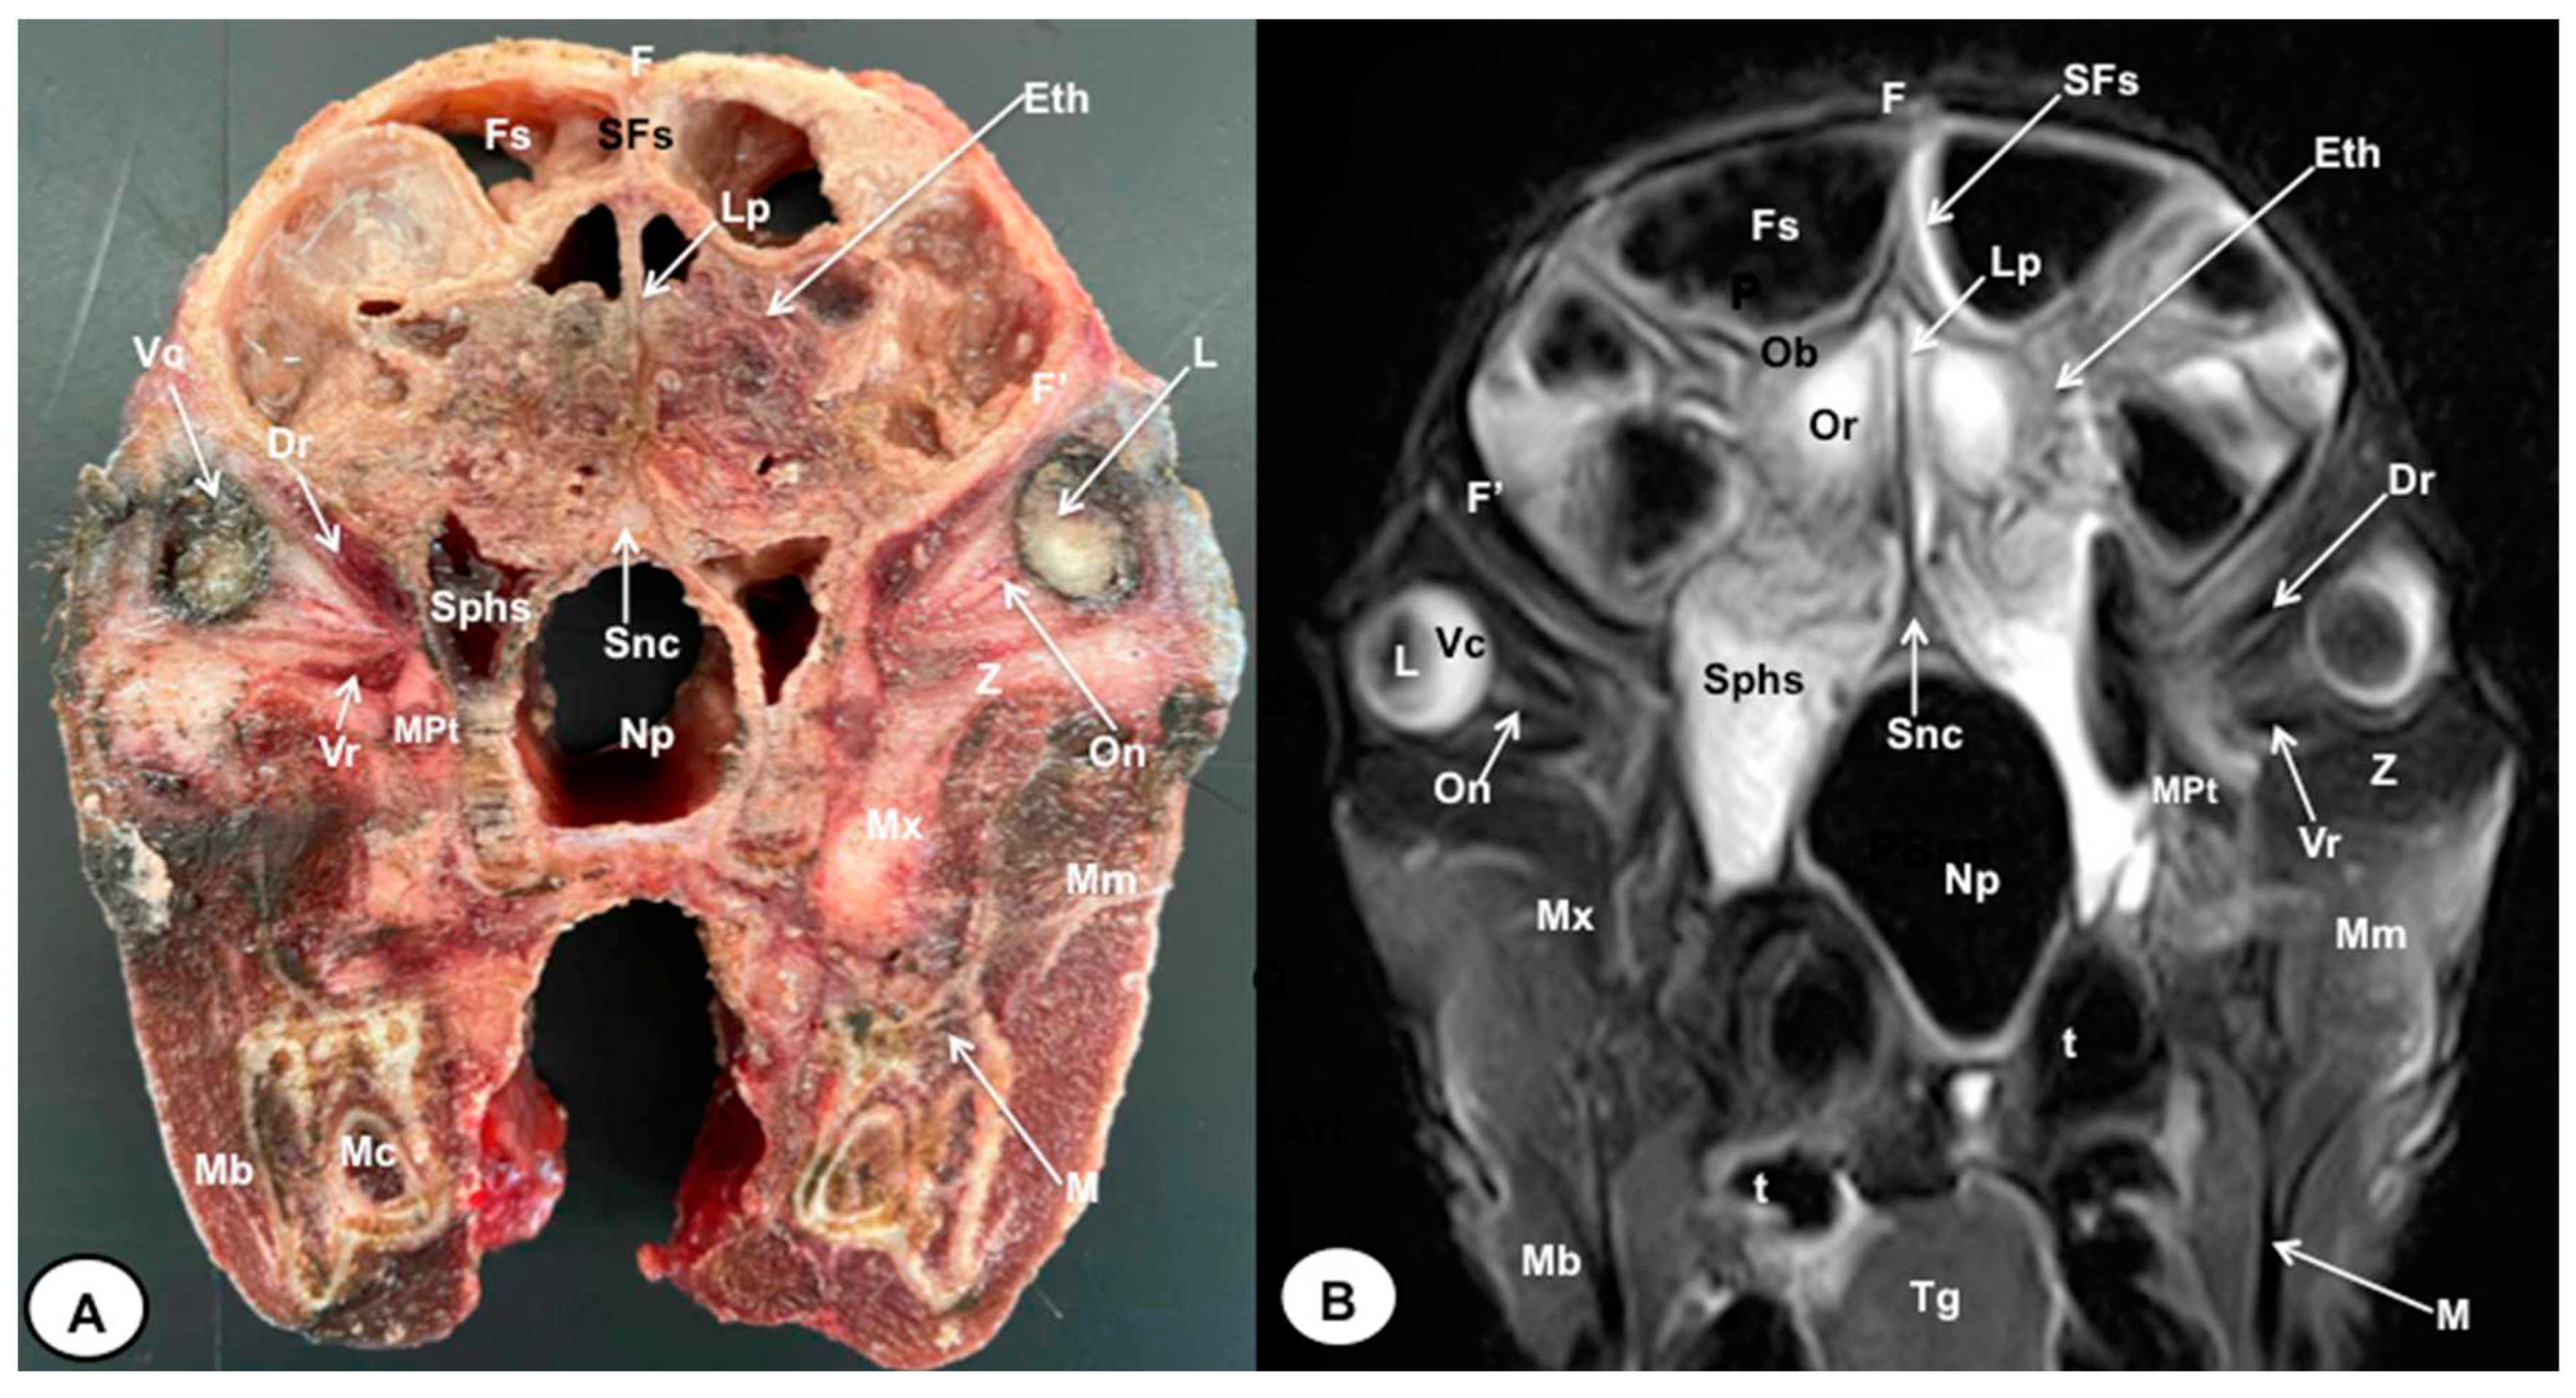

3.1. Anatomical gross-sections

3.2. Magnetic Resonance Imaging (MRI)